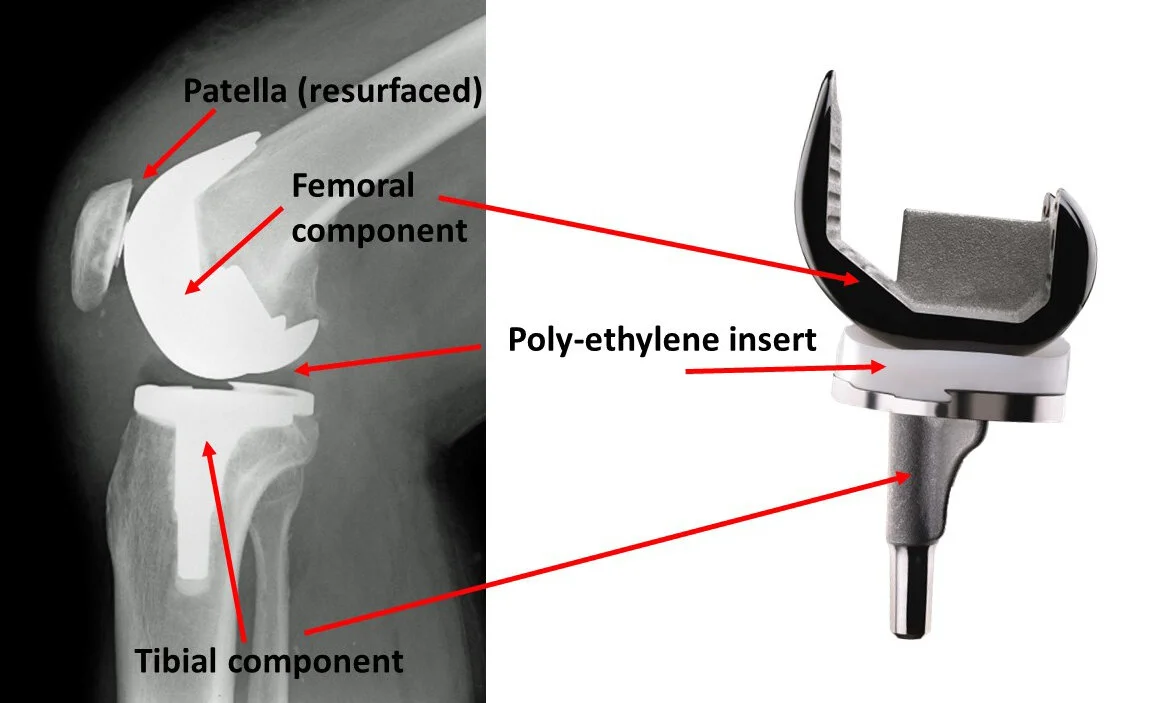

Knee Joint Prosthesis

Cemented Fixed Bearing TKR (PS/CR) is the Gold Standard across the globe.

Factors taken into consideration for knee joint prosthesis include:

1. Femoral Component

Designed & Contoured for Fixation in Distal Femur

Composition:

- Co-Cr-Mo: High strength, corrosion-resistant alloy

- Oxinium: Oxidised Zirconium exhibits exceptional wear resistance

Suitable for: Younger Population & Known Nickel Allergy

2. Tibial Component

Tibial Baseplate with Fins/Keels Contoured for Fixation in Proximal Tibia

Design: Asymmetrical (Anatomical) vs Symmetrical

Composition:

- Tivanium Alloy (Ti-6Al-4V)

- Co-Cr-Mo

3. Polyethylene Component

Specifically designed for fixation in tibial baseplate

Locking mechanism: Implant Specific

Radiolucent (Not Visible on X-Ray)

Composition:

- UHMWPE

- Vit E Doped UHMWPE

4. Bone Cement

High Viscocity Palacos Bone Cement is most commonly used

5. Patellar Component

UHMWPE with 3 peripheral lug holes for fixation in Re-surfaced Patella